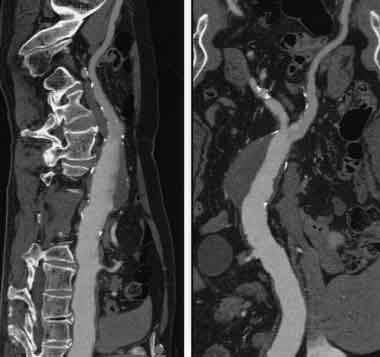

Проводим диагностику и лечение грыж любой формы межпозвонкового диска с помощью метода лазерной вапоризации.

Метод лазерной вапоризации выполняется, как правило, в амбулаторных условиях с использованием местной анестезии + внутривенное потенцирование. Чаще для местной анестезии используется 1% раствор лидокаина.

Под воздействием лазерного луча на конце световода создается высокая температура (от 200 до 400oС). Это приводит к образованию газа и пара, который выходит наружу через просвет иглы. При этом понижается внутридисковое давление, диск как бы сморщивается и грыжа, под действием возникающего «вакуум-эффекта», а так же, эластичности сохранившихся слоев фиброзного кольца и задней продольной связки, втягивается.

В этом и состоит основной смысл лазерной вапоризации или нуклеопластики. Как правило уже в процессе выпаривания больные отмечают уменьшения боли в пояснице.

Данная процедура занимает около 20-25 минут, после чего больному даются определённые рекомендации по лечению и больной уходит домой без госпитализации в стационар.

85% - 92% положительный эффект от данного лечения у больных с вертеброгенным синдромом.